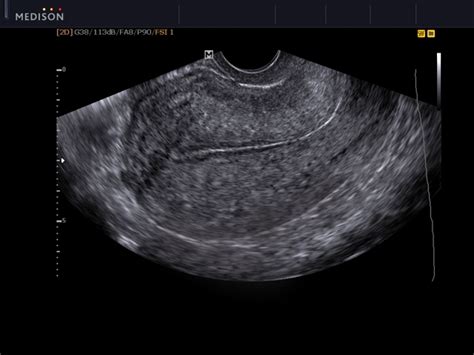

What Is a Cervical Polyp and What Does it Look Like? - HTQ from healthtopquestions.com By far the more common type is endometrial cancer, or cancer of the uterine lining (the endometrium). Uterine cancer symptoms are not something that should be overlooked. Also the lining would be thin without any masses. The entire uterus would look the same with out any fibroid s which would look like balls. Cancer that has spread to the cervix stage iii: Recurrence of vaginal cancer is usually more serious and may reoccur in other areas of the body. Endometrial cancer, the most common form, begins in the inner lining of the uterus. Vaginal cancer also tends to reoccur even after treatment.